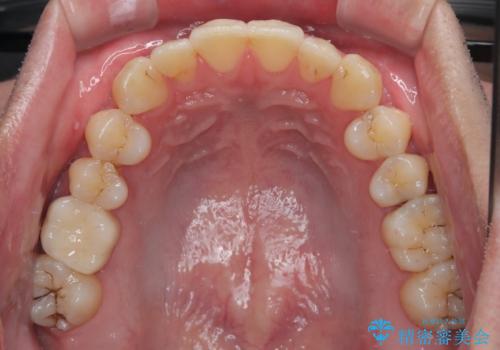

上下のデコボコを治したい インビザラインによる矯正治療

- 前歯のデコボコと突出感を気にして来院された患者様です。

極力目立たない装置を希望とのことで、インビザラインを用いて非抜歯で矯正治療を行うこととしました。

事前に親知らず4本を抜歯し、多少歯列を後方に移動できるように準備をした上で、なるべく歯と歯の間を削ることなくデコボコを解消できるように計画しました。